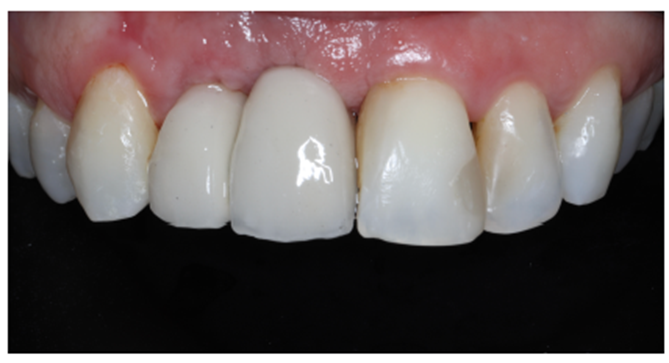

Após 4 meses, foi realizada radiografia panorâmica para o momento de abertura dos implantes (Figura 20). Foi planejado e escolhido os munhões da linha Smart Implacil (3.3x4x2.5) e confeccionadas duas coroas metalocerâmicas do tipo parafusada, visando maior possibilidade de reversibilidade e manutenção (Figuras 21 e 22).